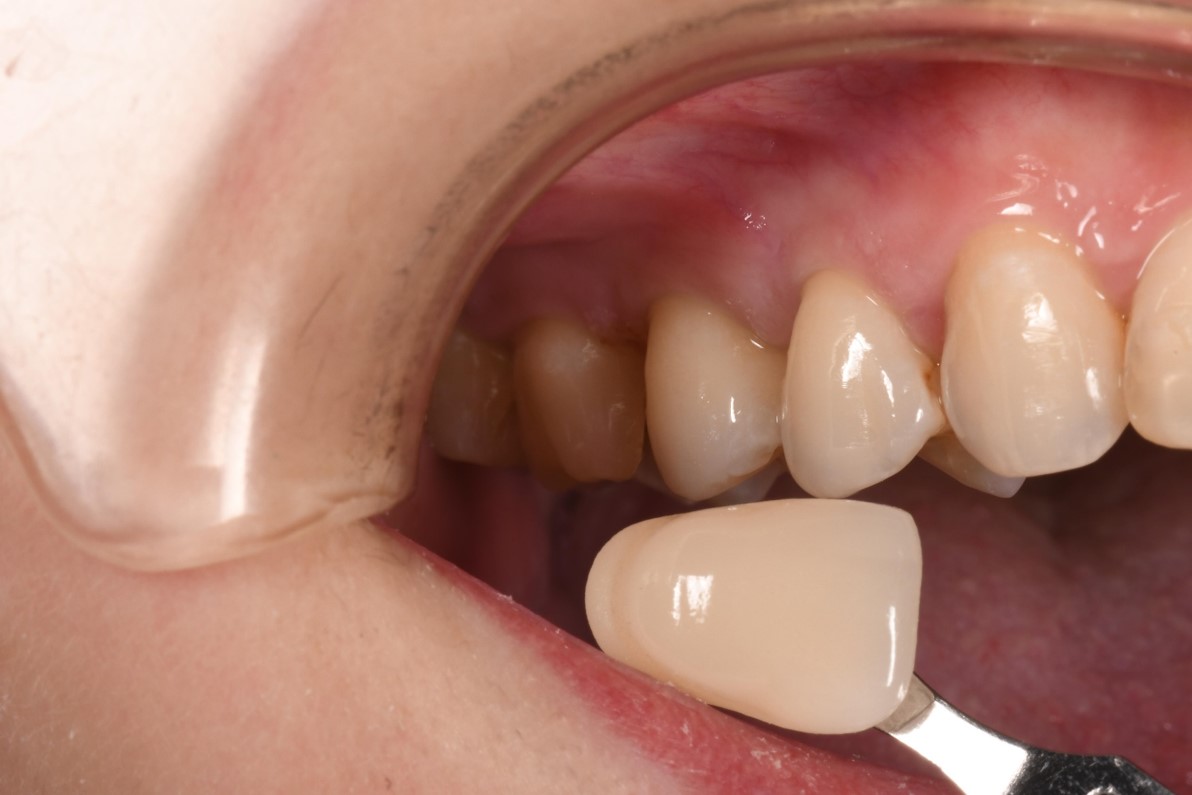

照相比色